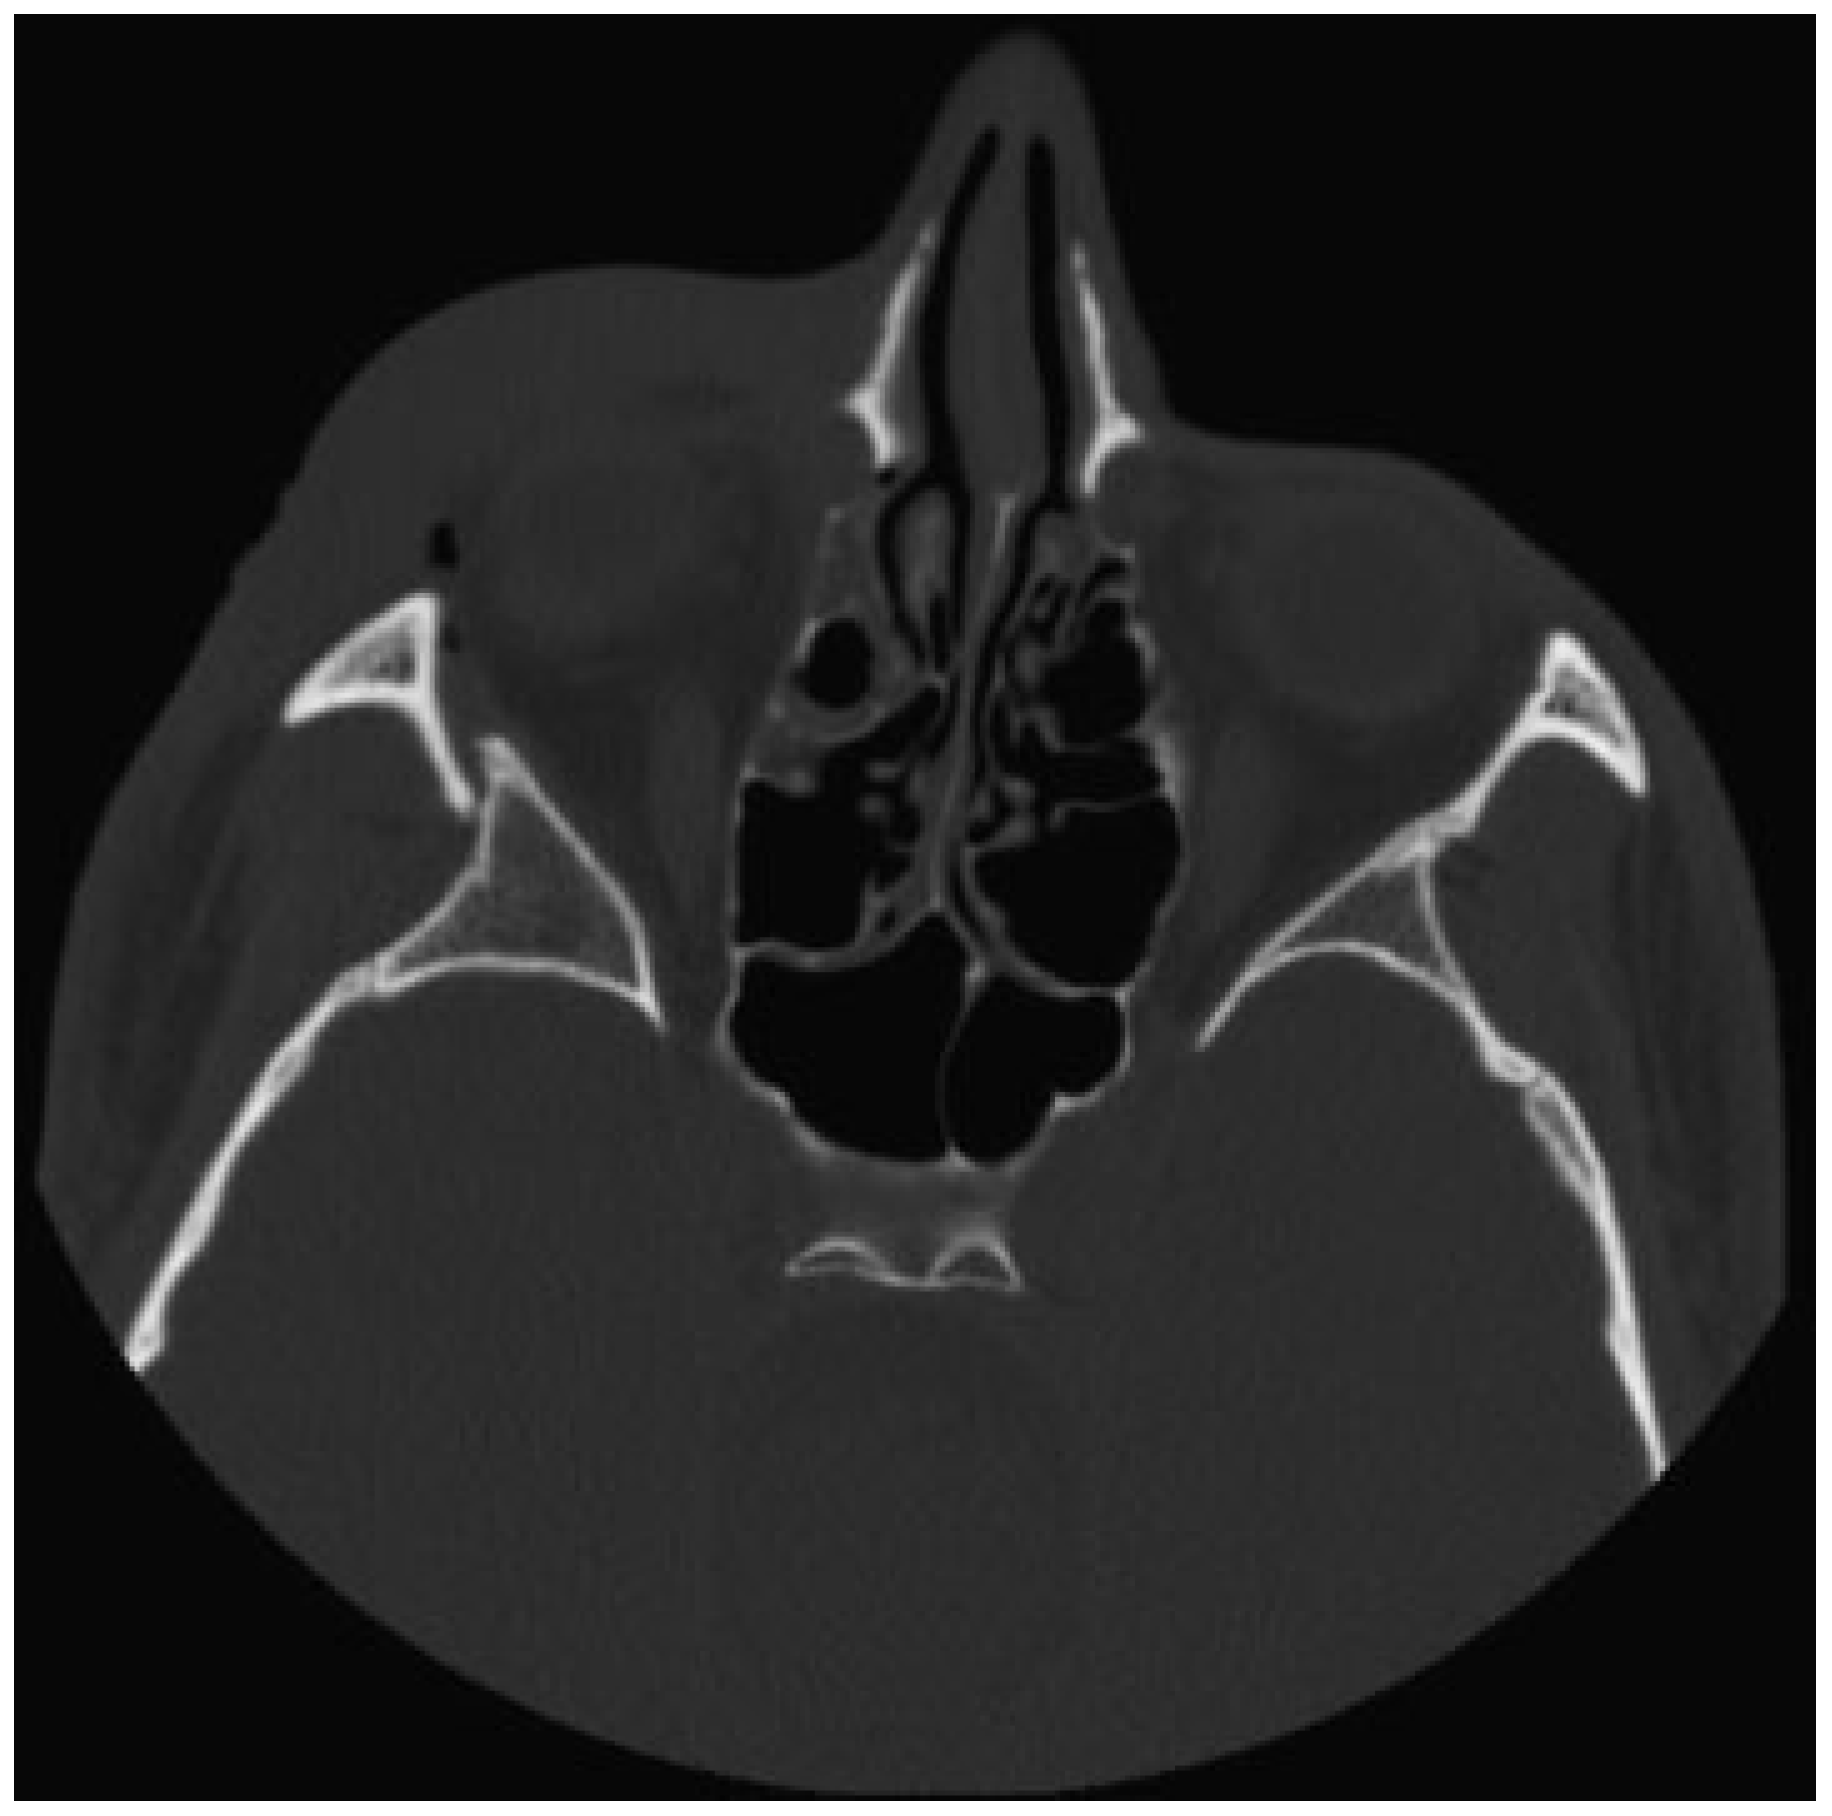

The authors defined simple LOWF as any fracture consisting of two boney pieces (Figure 1) and comminuted fractures as any fracture consisting of three or more pieces (Figure 2). Only patients who sustained fractures through primary trauma were included in this study. This excluded patients whose fractures were due to tumor resection or patients with a history of previous fractures of the lateral orbit. The senior investigator (W.S.) of this study identified the presence of all fractures, which were also confirmed upon review of the official radiology report.

Figure 1.

Simple lateral orbital wall fracture.